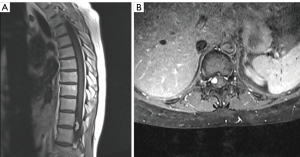

The author immediately ordered a thoracic lumbar spine MRI which revealed an intradural extramedullary circumcised oval-shaped mass measuring approximately 1.9 cm × 0.8 cm × 0.5 cm, as shown in Figure 1A,1B at T11-T12 with enhancement. The spinal MR angiography was performed to rule out a variant arterial malformation such as AV fistula. The test was concluded negative.